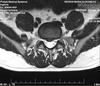

HDL L5-S1 with sciatica on right foot

Two years later, i have done another MRI which showed a small protusion only (the HDL was "gone"). I was feeling great!

Good luck, Daniel. I hope this contributes. It's not a large herniation.